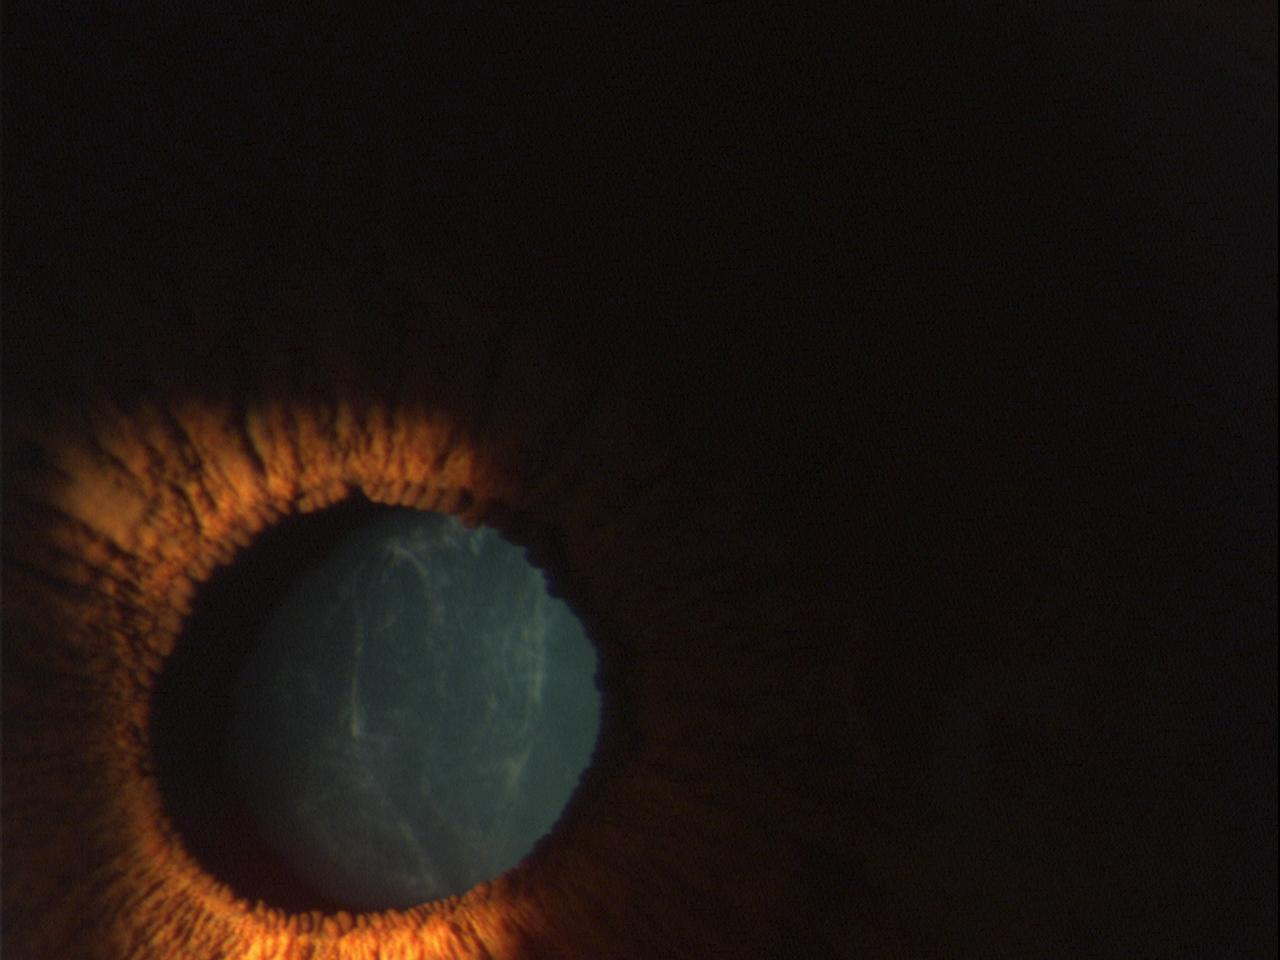

Figure 3 of Kotoulas, Mol Vis 2011; 17:2776-2781.

Figure 3. Cataract formation in case II:6.